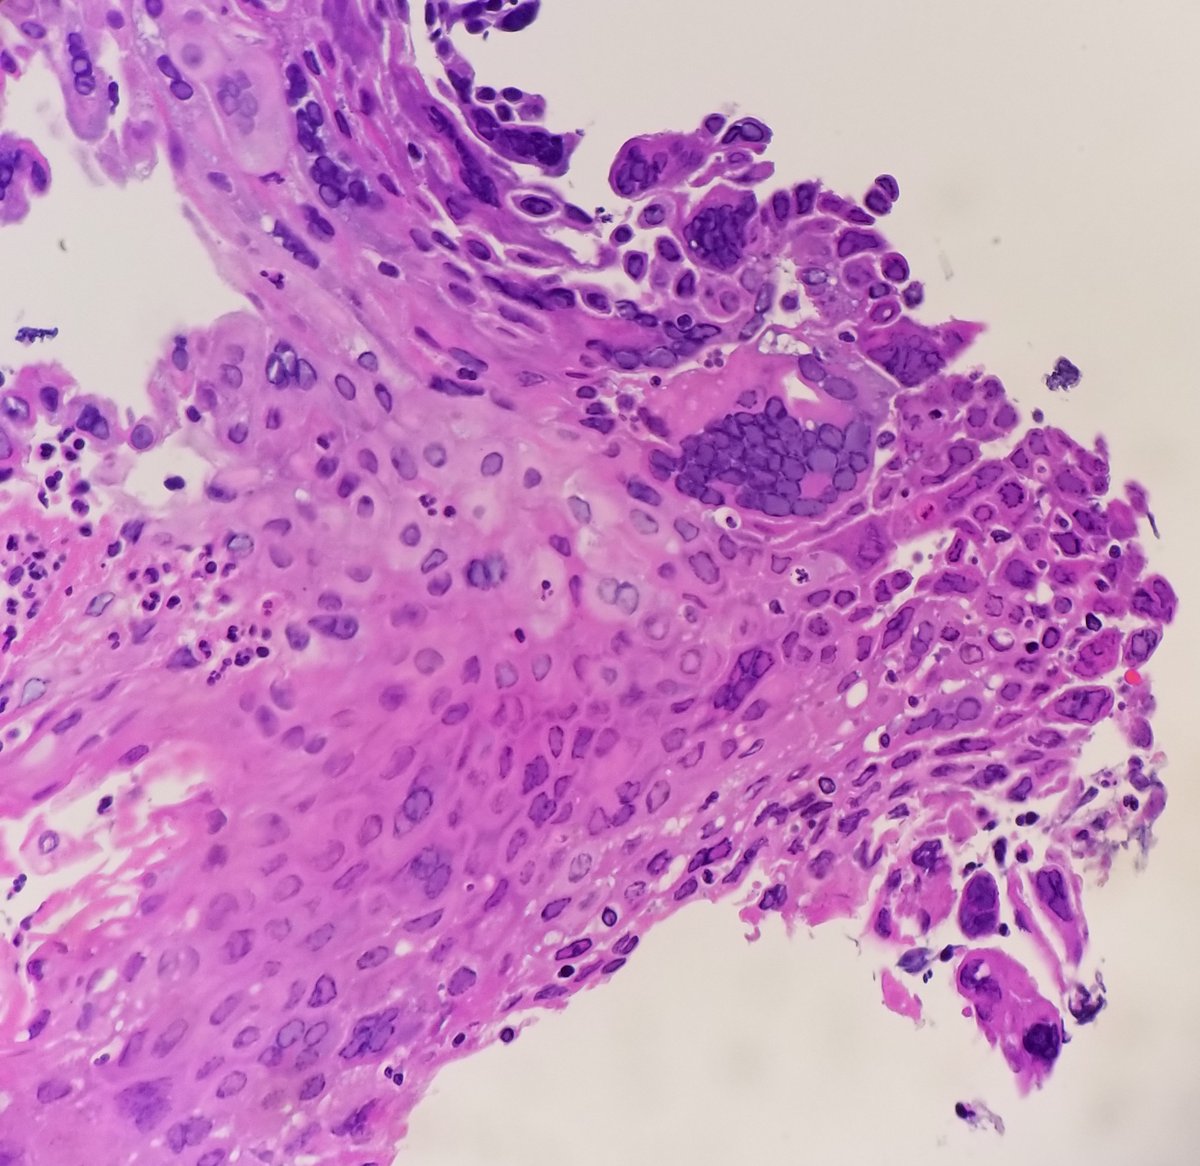

Pathology Outlines Herpes Simplex Esophagitis

Pathology Of Herpes Simplex Virus Infection Dr Sampurna Roy Md

File Herpes Esophagitis Intermed Mag Jpg Libre Pathology